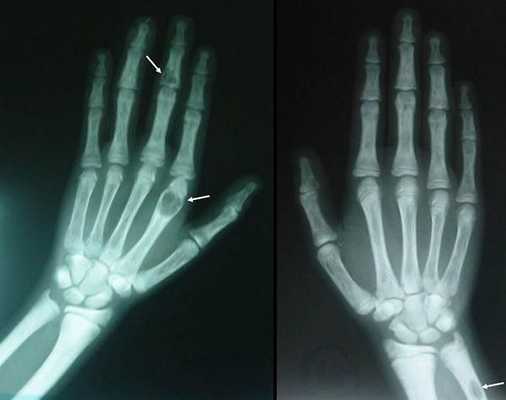

(Слева) Рентгенография в ЗП проекции: определяются резорбтивные изменения при гиперпаратиреозе (ГПТ). Компактное вещество на лучевой и локтевой поверхностях средних фаланг имеет кружевоподобный вид вследствие поднадкостничной резорбции и интракортикальной туннелизации. Резорбция головок II и V дистальных фаланг.

(Справа) Рентгенография в ЗП проекции: определятся субхондральная резорбция краев ДМФ суставов. Коллапс прилежащих суставных поверхностей имитирует эрозии. При прошлом исследовании определялась поднадкостничная резорбция, в настоящее время разрешившаяся. (Слева) Рентгенография в боковой проекции: картина «соли и перца» в костях черепа в результате генерализованной, но неравномерной резорбции костной ткани в сочетании с очагами склероза, имеющими неровные контуры. Обратите внимание на потерю дифференцировки наружной и внутренней пластинок черепа.